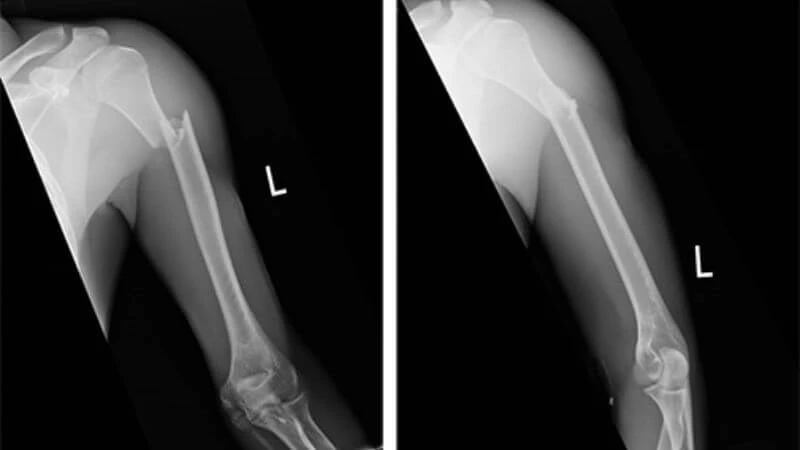

Cách chẩn đoán gãy xương

Khám cận lâm sàng

• X-quang là phương pháp chính để xác định tình trạng gãy xương.

• Trong trường hợp cần thiết, có thể thực hiện CT scan để có cái nhìn rõ hơn về tình trạng xương.